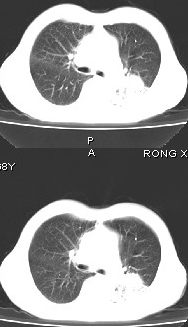

男68岁,反复发热、咳嗽,咯痰1月,曾有咯血史,双肺闻及呼吸音增粗。

左肺上叶尖后段及下叶多发实变阴影,内见支气管充气征,段以上支气管尚通畅,肺门区未见软组织肿块影,结合病人有反复发热病史,首先考虑感染性病变(干酪性肺炎不能排除),建议抗炎治疗后复查或结合纤支镜检查。

左肺上叶尖段及下叶干酪性肺炎可能性大,建议结合临床相关检查.右肺中叶炎症.建议治疗后复查.

该患者在25天前外圆平片见右肺中上肺野大片状影,(治疗不祥,在反复问病史后患者告诉;近一月住在新房内,搞装修),我认为首先考虑是感染,而且过敏性肺炎可能性大。